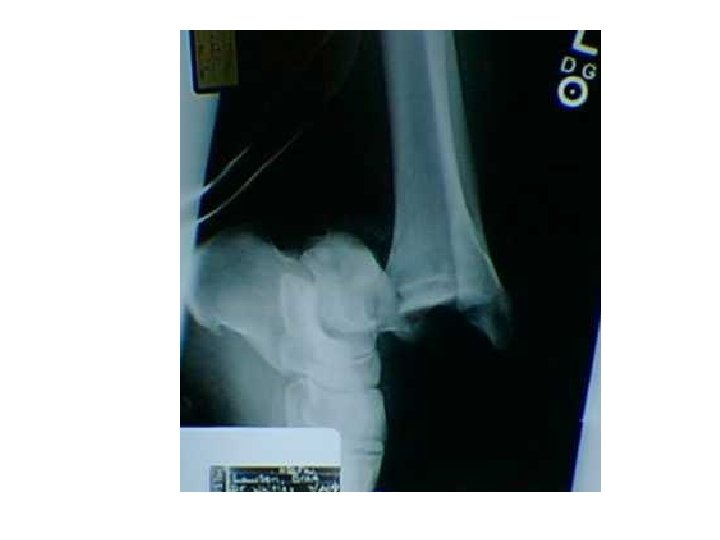

Ankle dislocation with no fractures. This takes a high degree of trauma and force. In this case this was generated as the result of a high flip off of a trampoline and impact with the ground. The ankle was in a plantar flexion and inverted position upon impact. This was an open dislocation.